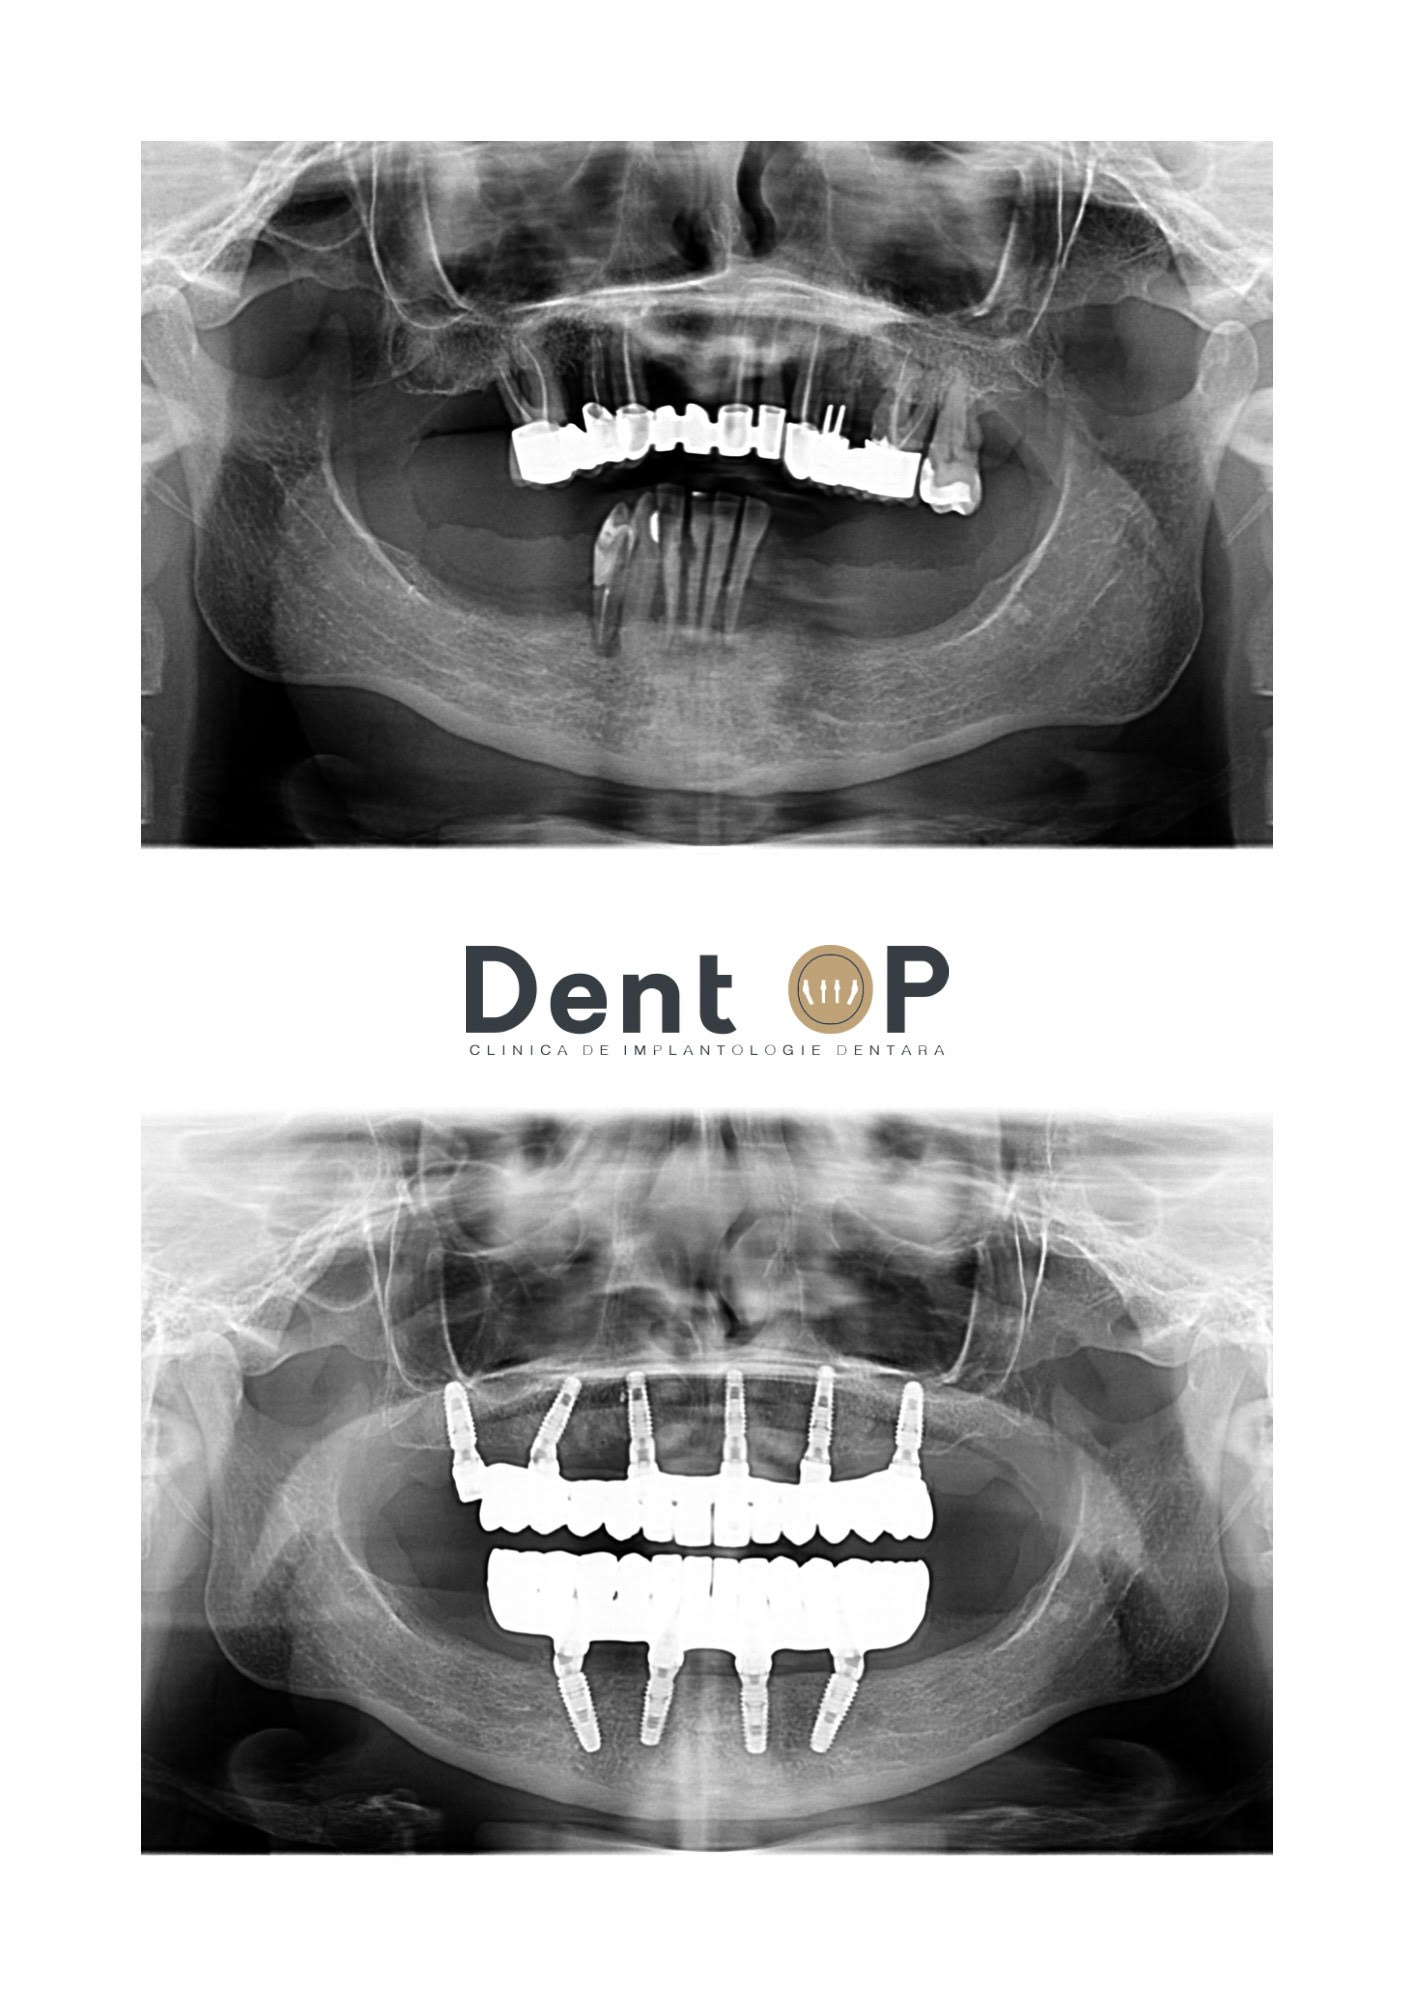

Pacienta s-a prezentat cu o serie de lucrări vechi la maxilar și pungi de puroi cauzate de boala parodontală. În radiografiile de mai jos putem observa starea danturii sale înainte de începerea procedurii, iar apoi la 6 luni după.

În cadrul intervenției, Dr. Cazacu Corrado a decis inserarea a 6 implanturi la maxilar și 4 la mandibulă de reabilitare totală într-o singură ședință cu Sedare Conștientă. Această procedură este special concepută pentru a face pacientul să nu simtă nimic pe parcursul operator.